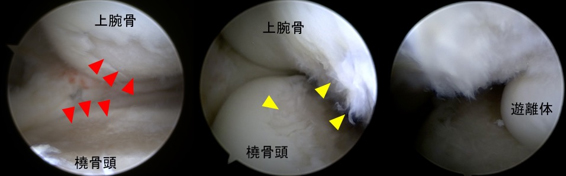

非荷重関節である上肢の関節は腰や膝などと異なり変形する頻度は低いですが、高齢化に伴いその頻度は少しずつ増えています。またスポーツやいわゆる肉体労働をされる方においては若年であっても変形することがあります。変形性関節症に対する関節鏡手術、人工関節手術も積極的に行っています。とくに肘の関節鏡手術は手術侵襲が小さい割には患者の満足度は高く、慢性的な肘の痛みでお悩みの方は一度ご相談いただければと思います。肩については、近年開発された肩の特殊な人工関節(リバース型)が導入され、変形性肩関節症の方に施行し良好な成績が得られています。

・変形性肘関節症の関節鏡所見

(左:前方鏡視、中:後方鏡視、右:肘関節内遊離体)

赤三角部:軟骨が欠損して骨が露出しています

黄三角部:軟骨が線維化し毛羽立っています -